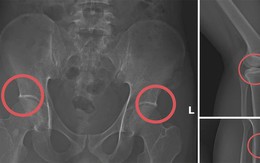

Tự đục vỡ xương để trục lợi bảo hiểm: Quá sợ kẻ vì tiền mà độc ác với chính mình

Nhịp sống mới 2025-11-17T13:59:00Chịu đục xương để trục lợi bảo hiểm, với chính cơ thể mình mà còn đối xử tàn nhẫn như vậy thì họ sẽ đối xử ra sao với người khác khi có cơ hội kiếm lợi?